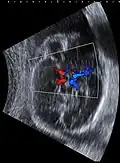

Diagram of the arterial circulation at the base of the brain (inferior view), the circle of Willis is drawn in the upper half. Blood flows up to the brain through the vertebral arteries and through the internal carotid arteries.

The circle of Willis (also called Willis' circle, loop of Willis, cerebral arterial circle, and Willis polygon) is a circulatory anastomosis that supplies blood to the brain and surrounding structures in reptiles, birds and mammals, including humans.[1] It is named after Thomas Willis (1621–1675), an English physician.[2]

The circle of Willis is a part of the cerebral circulation and is composed of the following arteries:[3]

The arrangement of the brain's arteries into the circle of Willis is believed to create redundancy (analogous to engineered redundancy) for collateral circulation in the cerebral circulation. If one part of the circle becomes blocked or narrowed (stenosed) or one of the arteries supplying the circle is blocked or narrowed, blood flow from the other blood vessels can often preserve the cerebral perfusion well enough to avoid the symptoms of ischemia.[7]